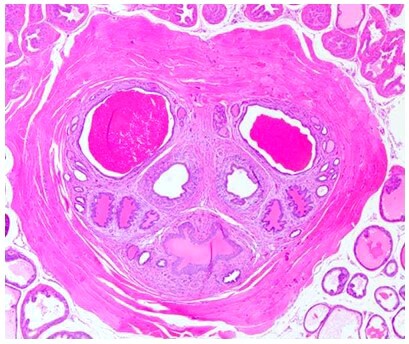

ÌṩͨÀýµÄʯÀ¯ÇÐÆ¬¡¢H&EȾɫÕï¶Ï£»£»£»

Ìṩ±ù¶³ÇÐÆ¬¡¢ÌØÊâȾɫ¡¢ÃâÒß×éÖ¯»¯Ñ§È¾É«¼°×éÖ¯½»Ö¯·´Ó¦£¨TCR£©µÈÕï¶ÏЧÀÍ£¬£¬£¬ £¬£¬Öª×ã¿Í»§¶ÔÌØ¶¨ÊÔÑéµÄ×éÖ¯ÊÓ²ìÐèÇ󡣡£¡£¡£¡£

• H&E

HEȾɫ.png

• ÌØÊâȾɫ

ÌØÊâȾɫ-·¬ºì¹ÌÂÌȾɫ.jpgÌØÊâȾɫ-PASȾɫ.png